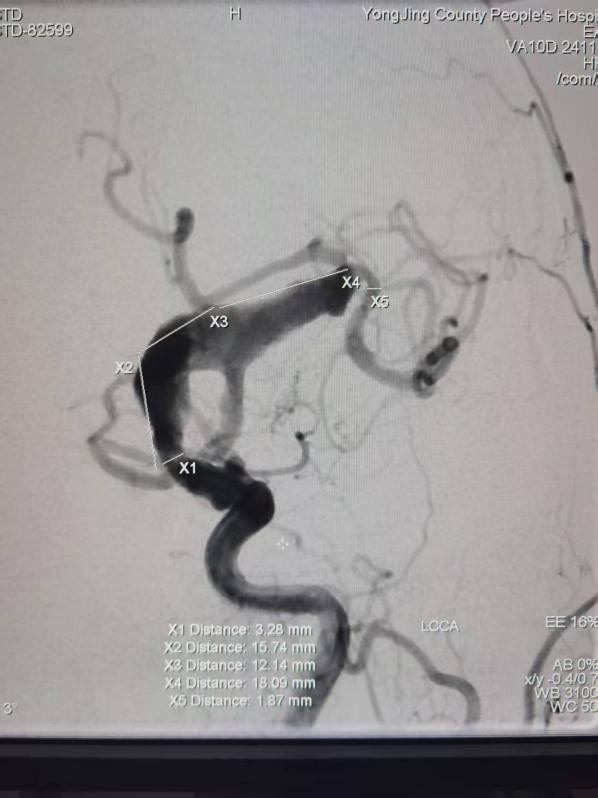

病例四:颅内巨大动脉瘤——拓展介入诊疗视野

一位因反复头痛就诊的患者,经CT血管成像检查,确诊为颅内巨大动脉瘤,形态不规则,破裂风险极高。面对这一急危重症,孔令超与当地医生共同分析病情,制定诊疗方案。

通过对该病例影像特征的细致观察与风险分层评估,孔令超对巨大动脉瘤的形态学特点、破裂风险因素及介入治疗适应证有了更系统的认识。结合自身技术优势,完成全脑血管造影术,拓展了他在脑血管疾病领域的临床视野,也为科室今后开展动脉瘤介入治疗积累了宝贵经验。